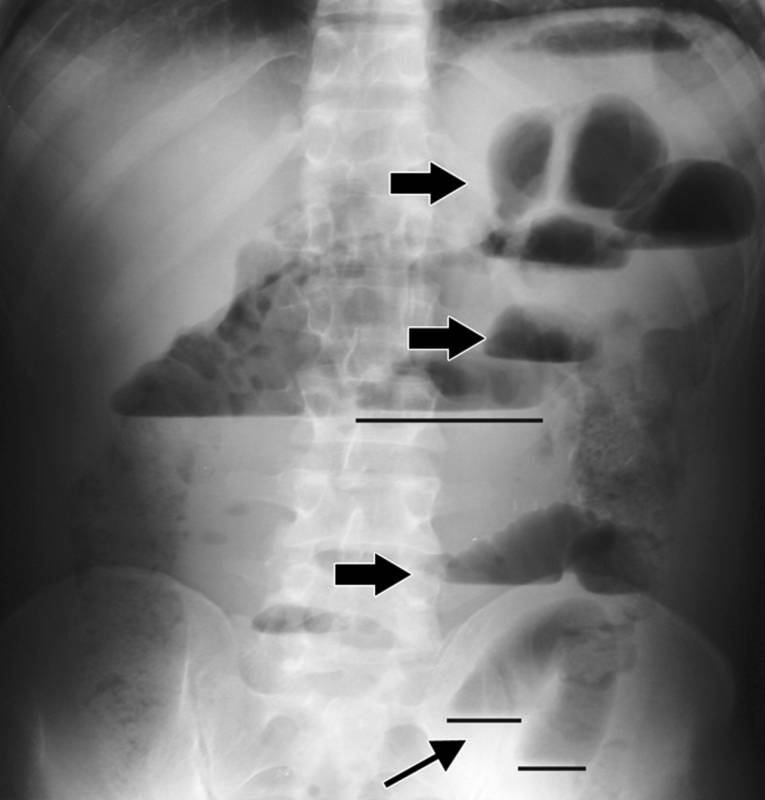

- рентгенологическое исследование органов брюшной полости (определяется поперечная исчерченность кишечника, уровни газа и жидкости в петлях);